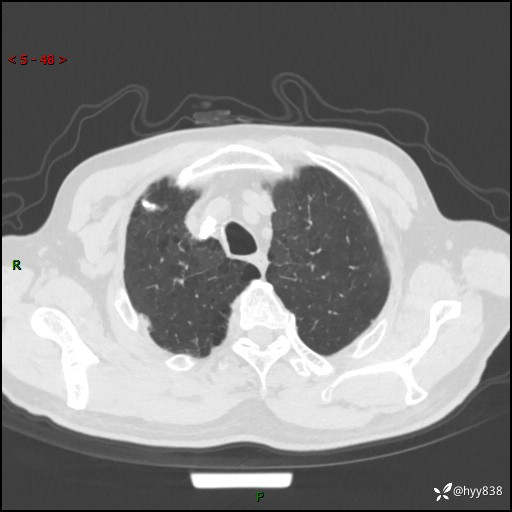

辅助检查:CT

胸部CT平扫